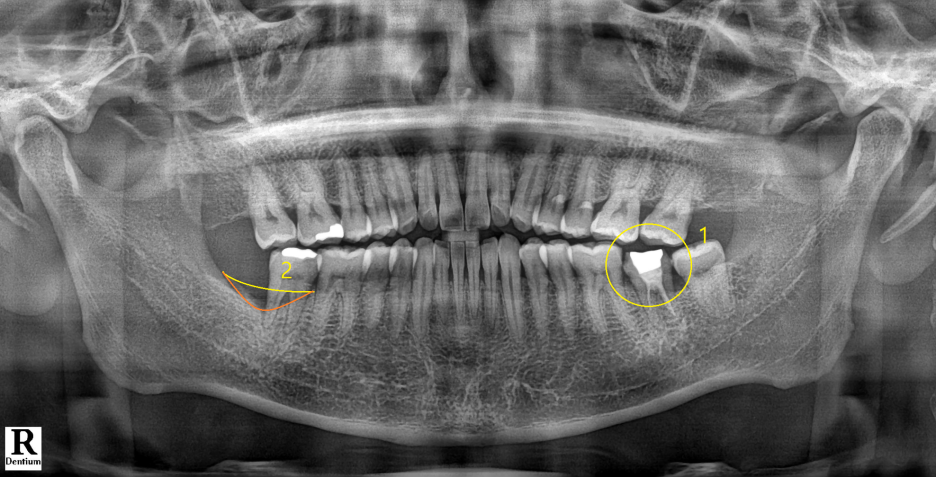

1번으로 표기된 해당 치아에 통증은 없었고, 파노라마 사진상으로도 치아 및 치주조직에 별다른 이상은 없어보였습니다.

다만 2번으로 표기된 부분은 추후 치주치료가 필요합니다.

해당 치아는 과거에 신경치료를 해둔 형태가 조금 미흡해보였습니다.

1번 근관의 경우 뿌리끝까지 흰색 재료, 흔히 Gutta percha 라고 하는 재료가 잘 채워져 있습니다.

2번 근관의 경우 뿌리끝까지 Gutta percha가 채워져 있지 않고 절반만 채워져 있는 상태입니다.